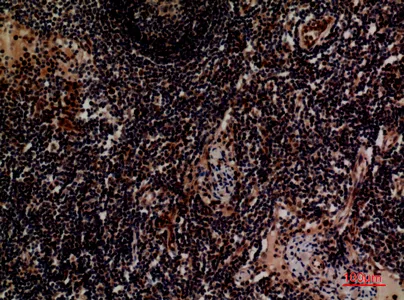

Integrin alpha 3 Rabbit Polyclonal Antibody

Cat: APRab00576

Size1:50μL Price1:$150

Size2:100μL Price1:$280

Size3:500μL Price1:$280

Application:WB,IHC-P,ELISA

Reactivity:Human,Mouse,Rat

Conjugate:Unconjugated

Gene Name:ITGA3

Size2:100μL Price1:$280

Size3:500μL Price1:$280

Application:WB,IHC-P,ELISA

Reactivity:Human,Mouse,Rat

Conjugate:Unconjugated

Gene Name:ITGA3